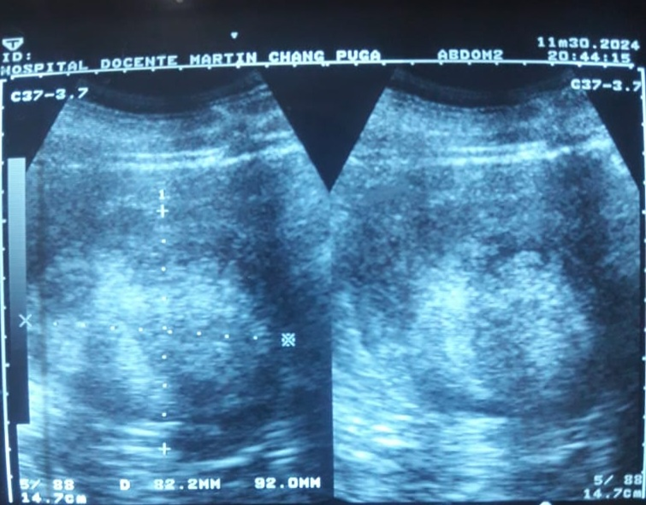

En el ultrasonido abdominal se observaron: el hígado, de aspecto homogéneo y tamaño normal; la vesícula biliar distendida, sin litiasis; la vía biliar en buenas condiciones. El páncreas no se vio por la interposición de gases. Los riñones presentaban tamaño y forma normales, con buena relación córticomedular. En el polo inferior del riñón derecho se observó una imagen de masa heterogénea, mayormente ecogénica, de 104 x 90 mm, irregular y con bordes mal definidos, circunscrita parcialmente, sin cápsula ecogénica visible, en el parénquima (Fig. 1).

Fig. 1 - Ultrasonidos abdominal y renal simples. Obsérvese la masa heterogénea, ecogénica en su mayor parte, en el parénquima del riñón derecho.

Estas características correspondían a una neoplasia sólida (aquística), sin hidronefrosis, ni invasión vascular aparente (Fig. 2).